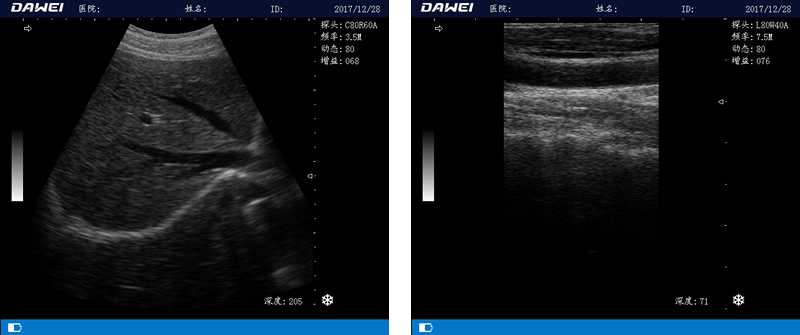

DW-580

筆記本全數字超聲診斷儀

1.優質的數字成像技術,圖像更清晰